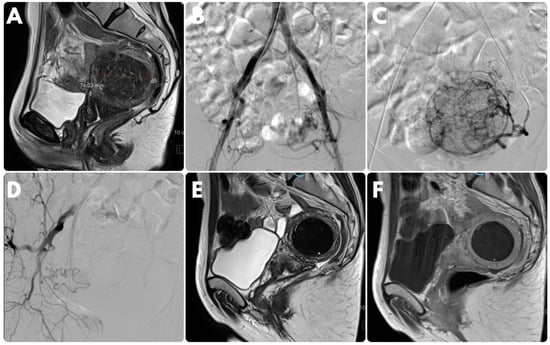

4. Endovascular Treatment